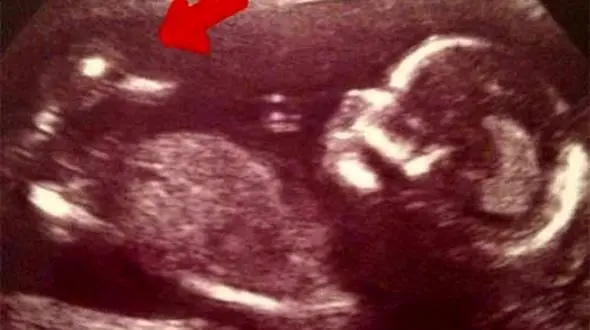

رکنا: این زن بارداری عجیبی را تجربه کرد.

رکنا: بارداری های دوقلویی سخت و دردناک است و زنان را در معرض خطرهای بی شماری قرار می دهد.